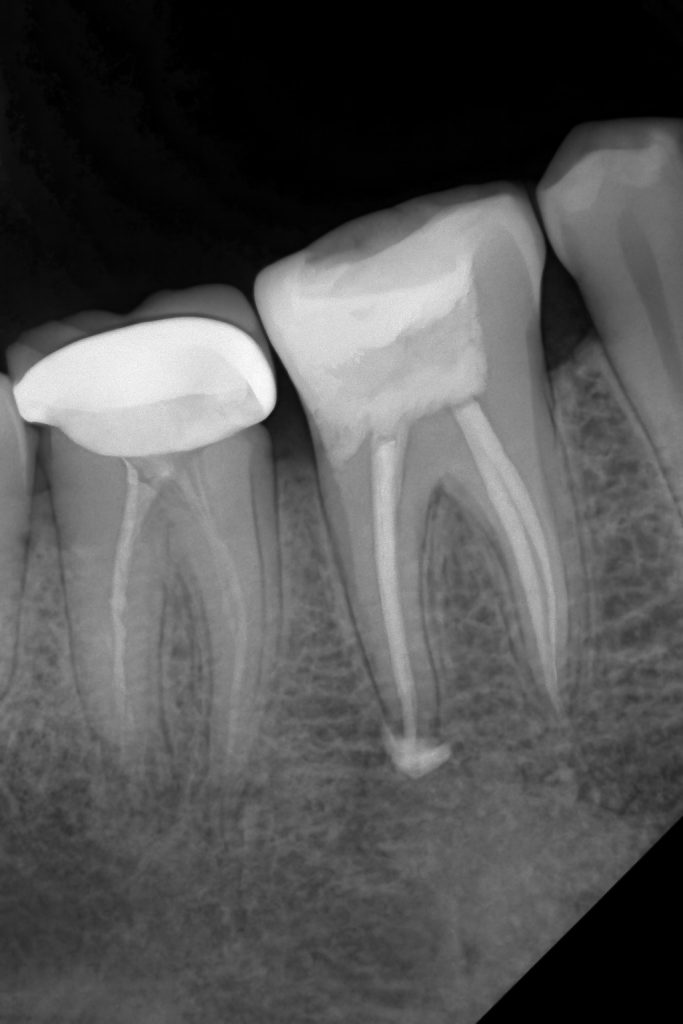

- Pre-operative radiographs confirmed canal anatomy.

- Obturation with warm vertical condensation.

- Immediate coronal seal ensured with flowable composite.

- Full control of deep margins without surgical crown lengthening.

- Biological width respected, tooth preserved, and long-term success enhanced.